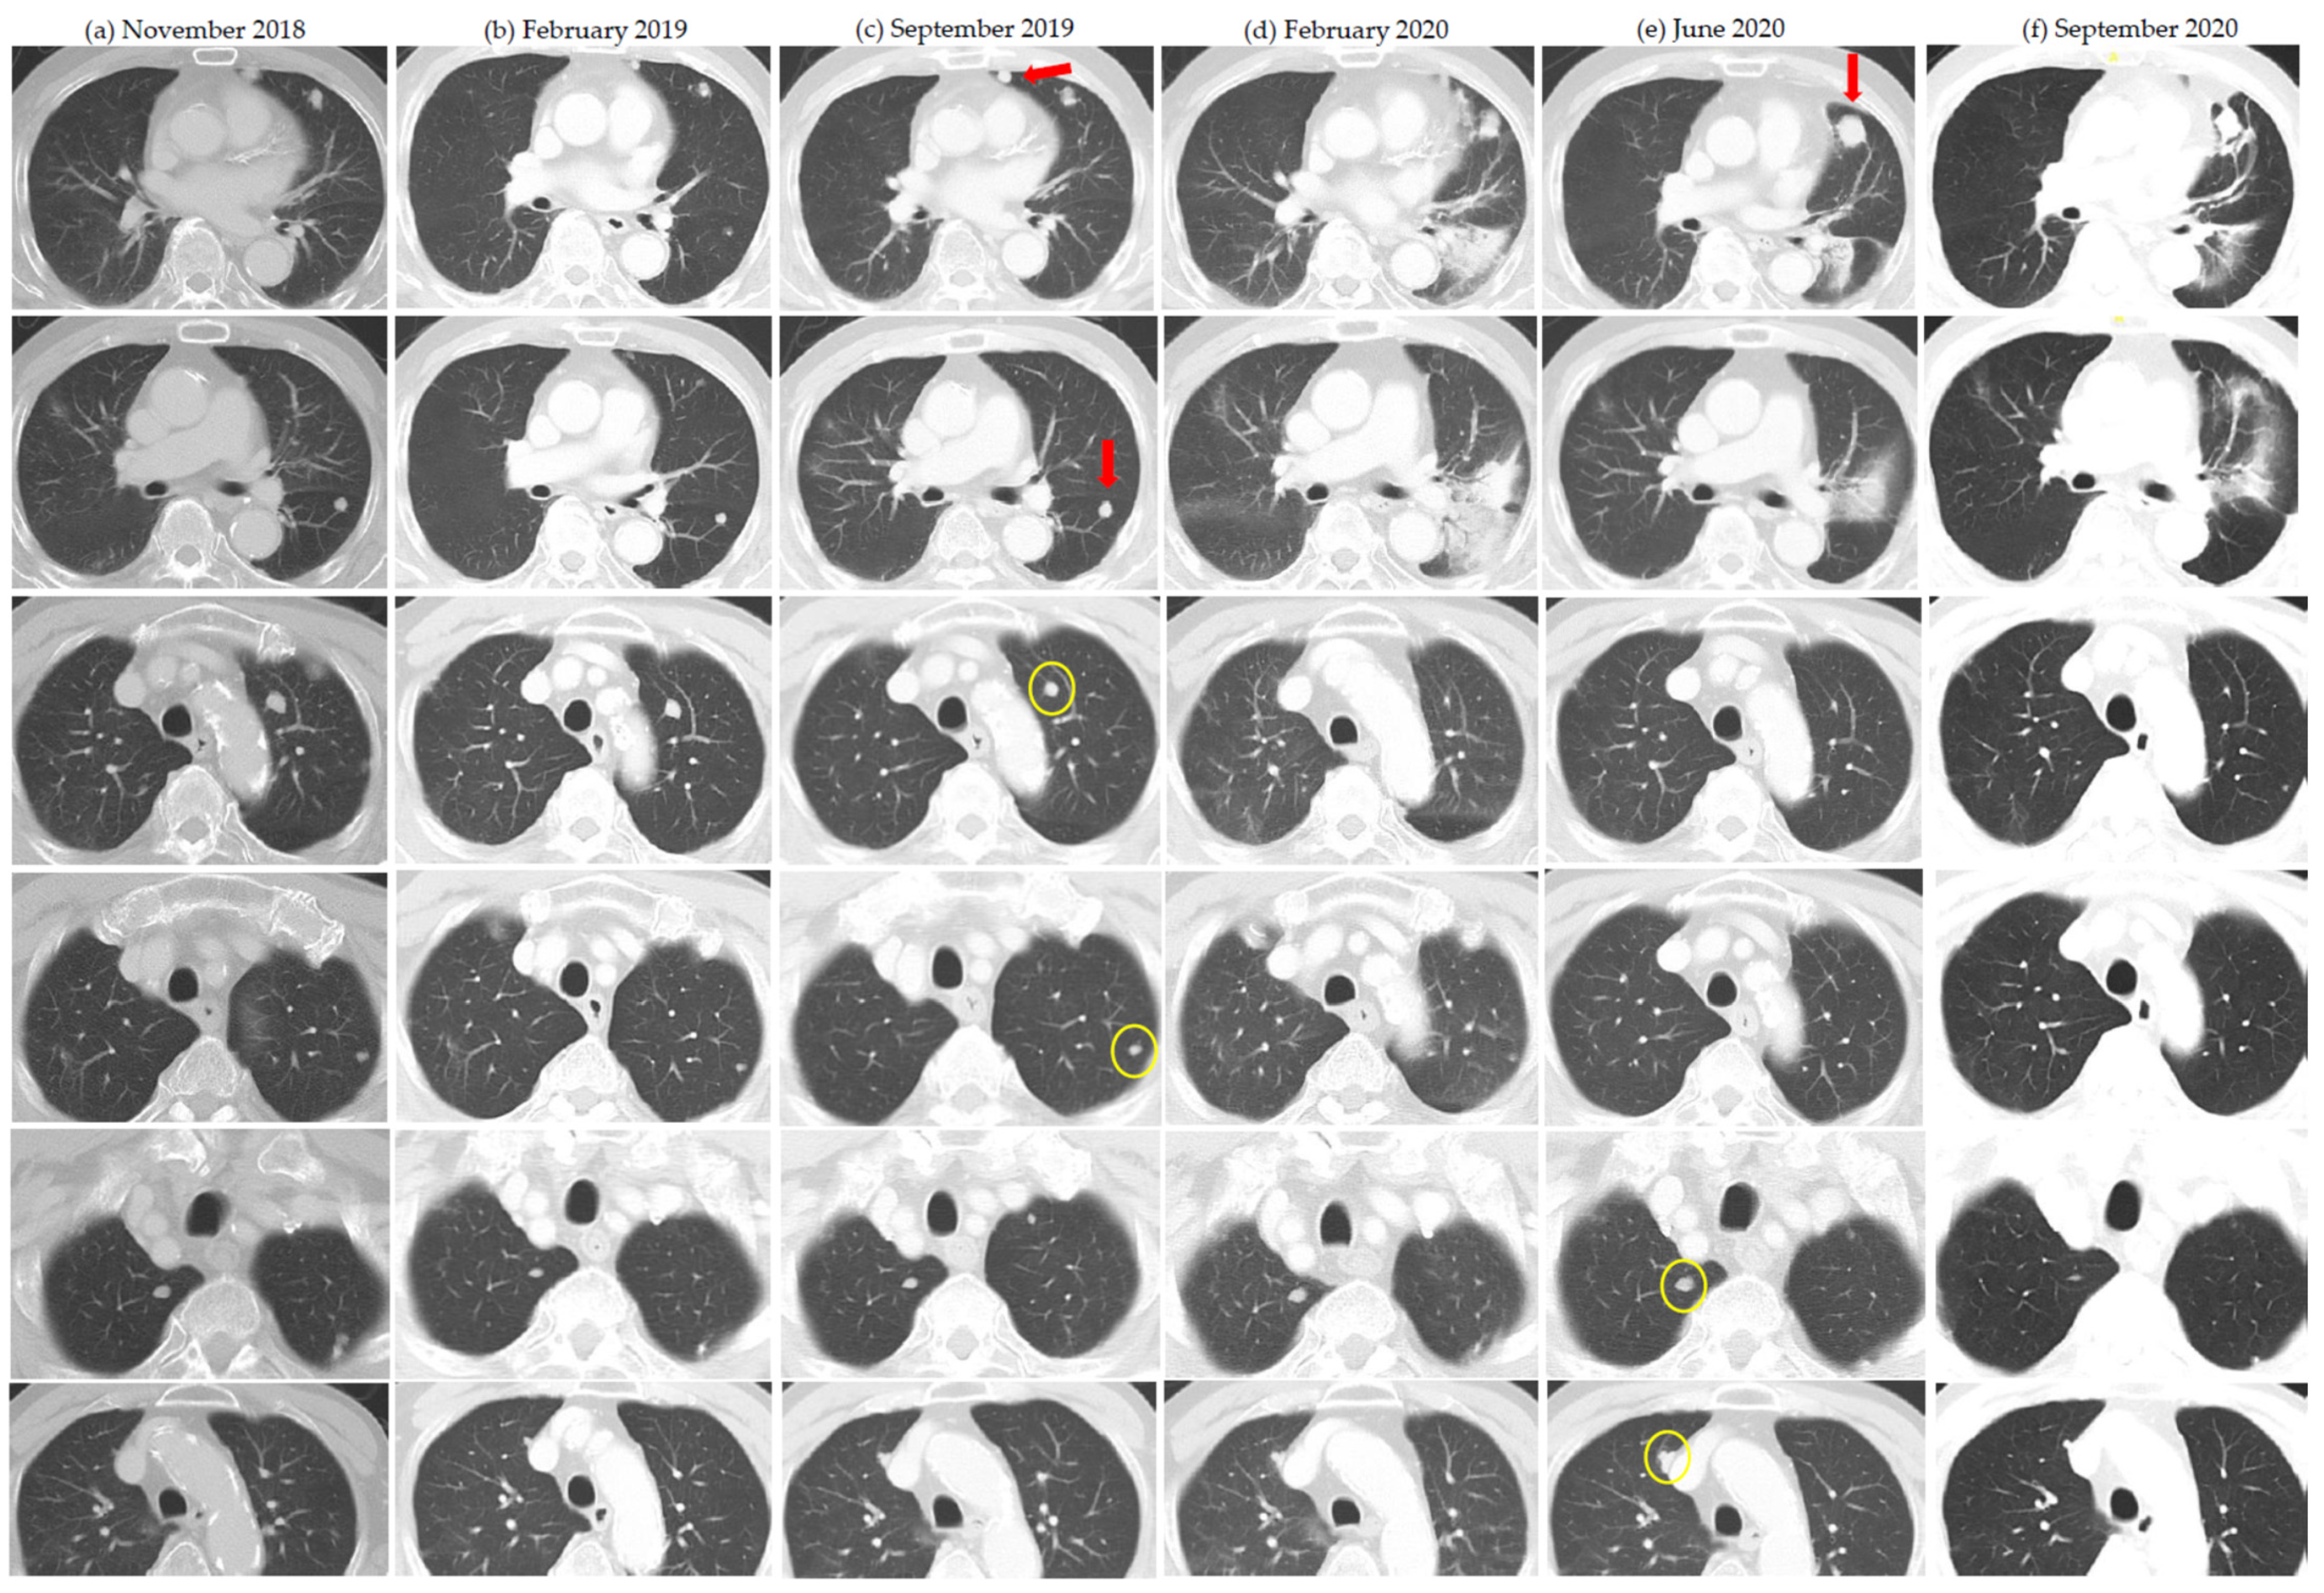

| 6 | Nivolumab | 17 26 | 54Gy/3 42Gy/5 25Gy/5 | Yes Yes | Lung Lung | Lung, 2 Lung, 2 | 5 3 | Prior spontaneous regression and dissociated response after cytoreductive nephrectomy |